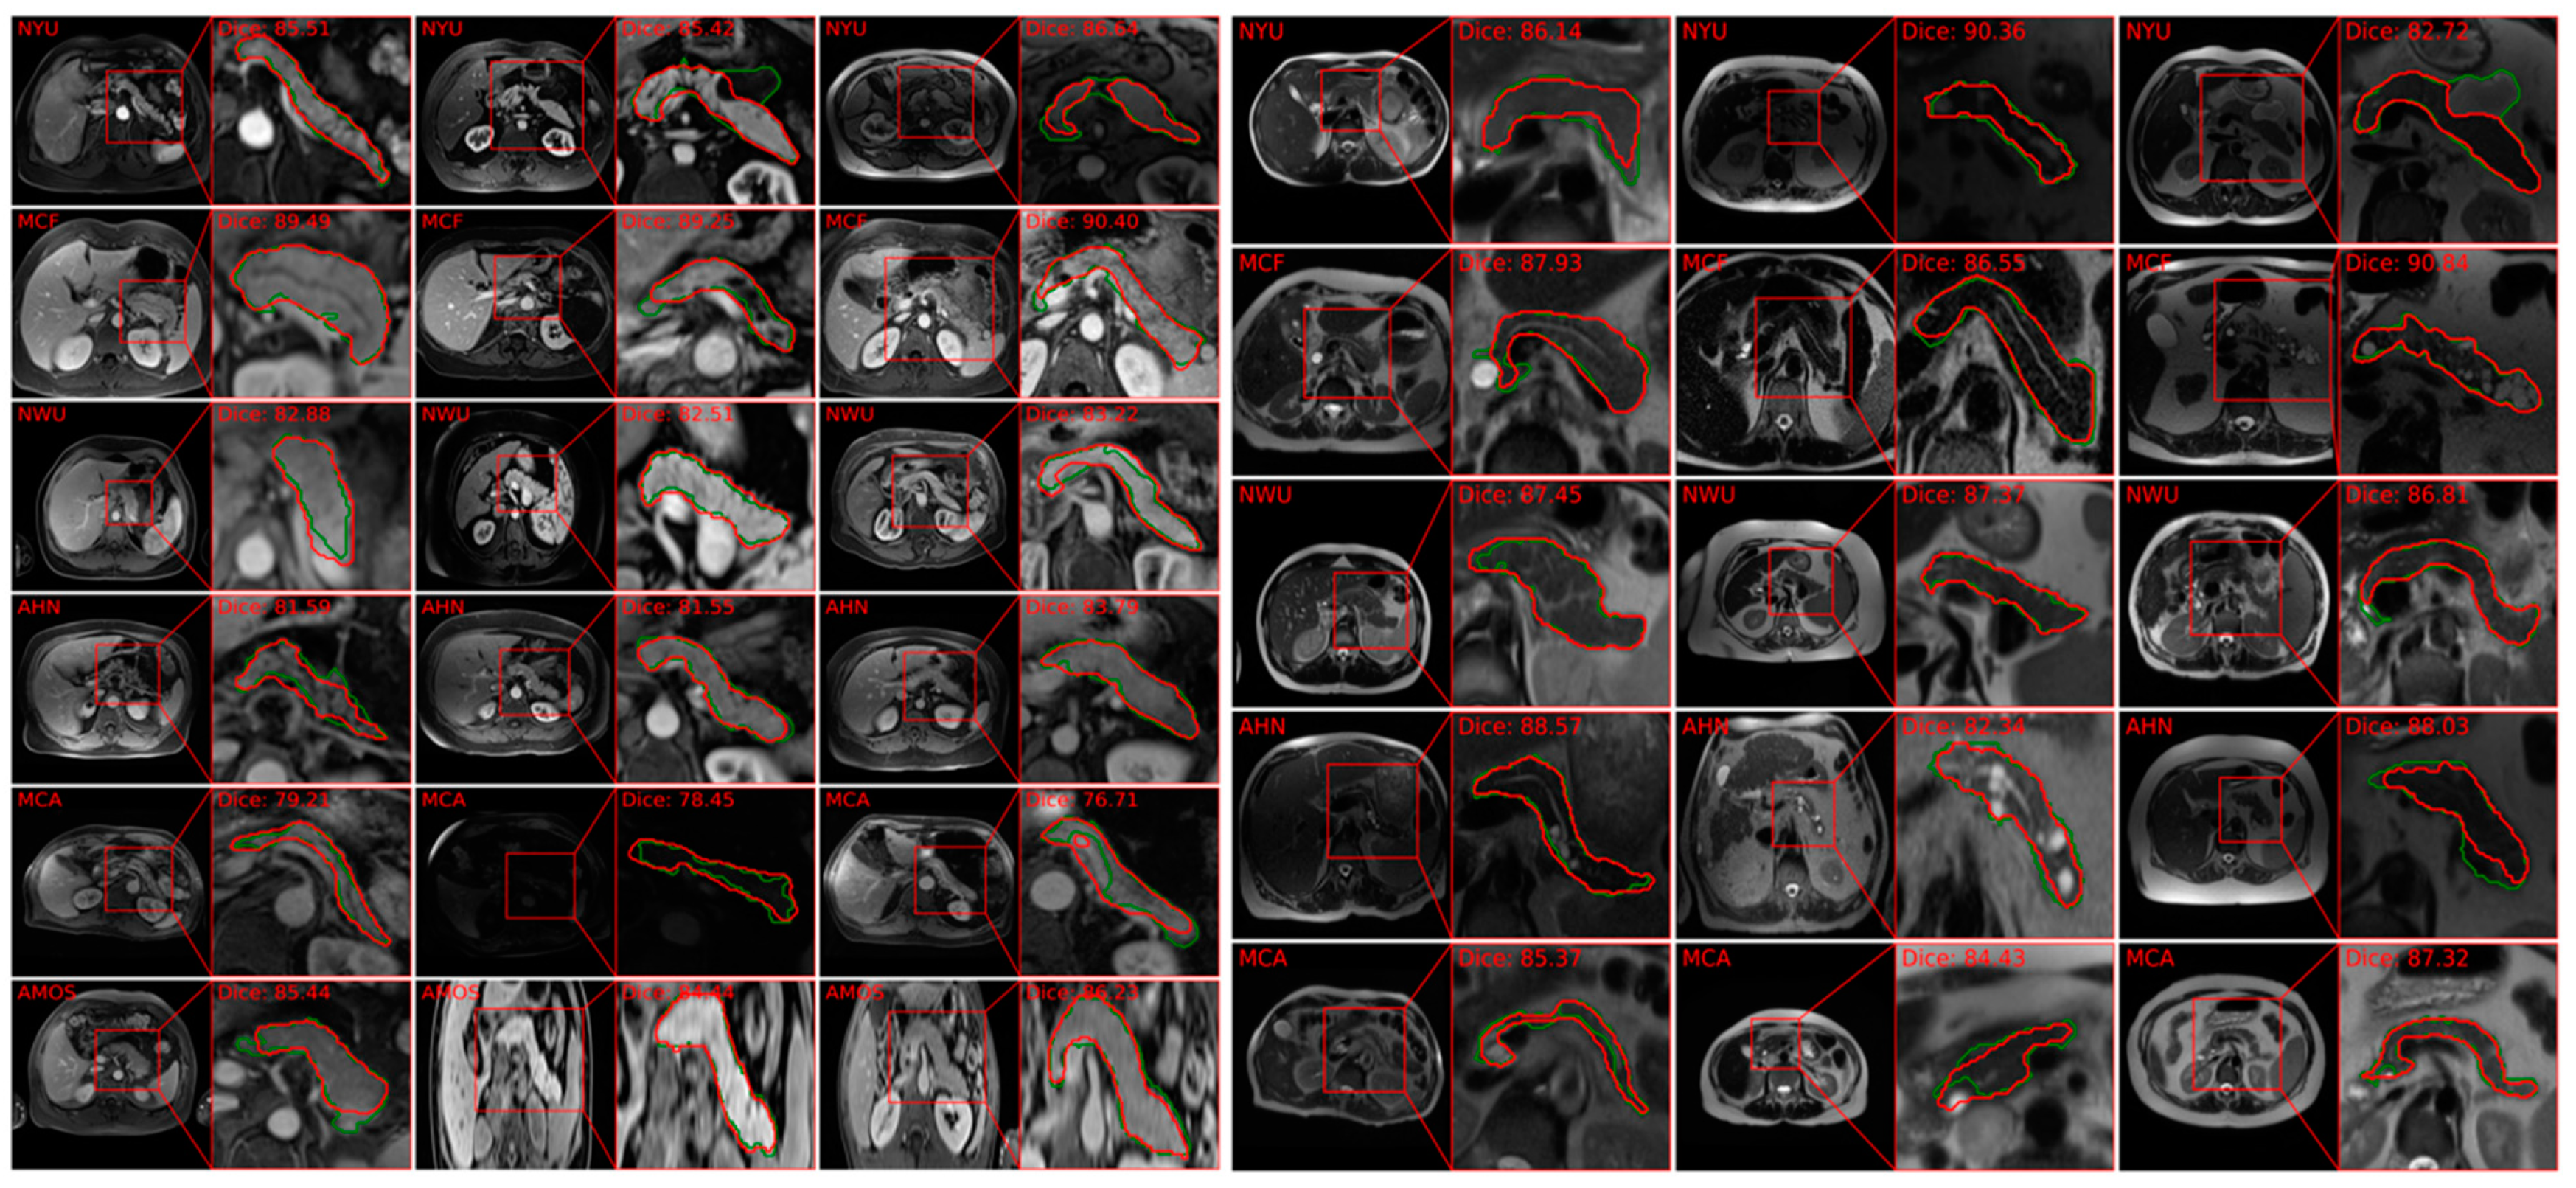

5.1.3. MRI-Based Studies (Segmentation and Diagnosis)

5.1.4. Segmentation of Pancreas from MRI

- Zhang, Z.; Keles, E.; Durak, G.; Taktak, Y.; Susladkar, O.; Gorade, V.; Jha, D.; Ormeci, A.C.; Medetalibeyoglu, A.; Yao, L.; et al. Large-scale multi-center CT and MRI segmentation of pancreas with deep learning. Med. Image Anal. 2024, 99, 103382. [Google Scholar] [CrossRef] [PubMed]

| Zhang [88] | Linear Transformer with nnU-Net (PanSegNet) | Pancreas body | 1350 CT scans and 767 T1 and T2 (made publicly available) | 88.3% for CT, 85.0% for MRI T1, 86.3% for MRI T2. |